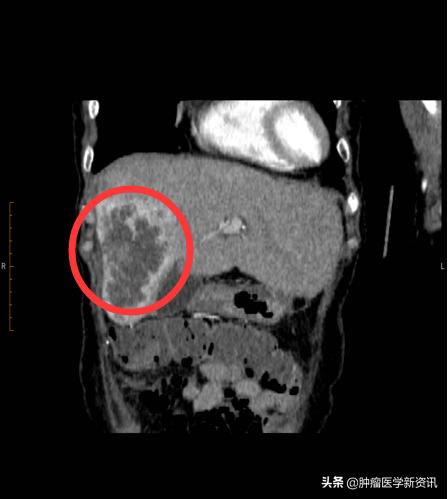

2020年3月,王女士母亲在持续进行2次iNKT癌症免疫治疗+肝部介入后,2个月的时间,王女士的母亲肝部10cm肿瘤缩小了1/3,肿瘤标志物下降接近一半,精神也越来越好,就连吃饭都比之前好多了,可以如正常人般生活了。

治疗后

看着母亲气色渐渐变好,王女士终于松了一口气,心里的大石头也慢慢落地。王女士说,母亲以前喜欢和邻居们一起外出散步,生病之后就很少再出门。虽然现在疫情期间无法外出,但是她有了更多的时间去陪伴母亲,一起摆弄院子里的花花草草。王女士相信她可以和弟弟一起,给予母亲幸福的晚年生活。